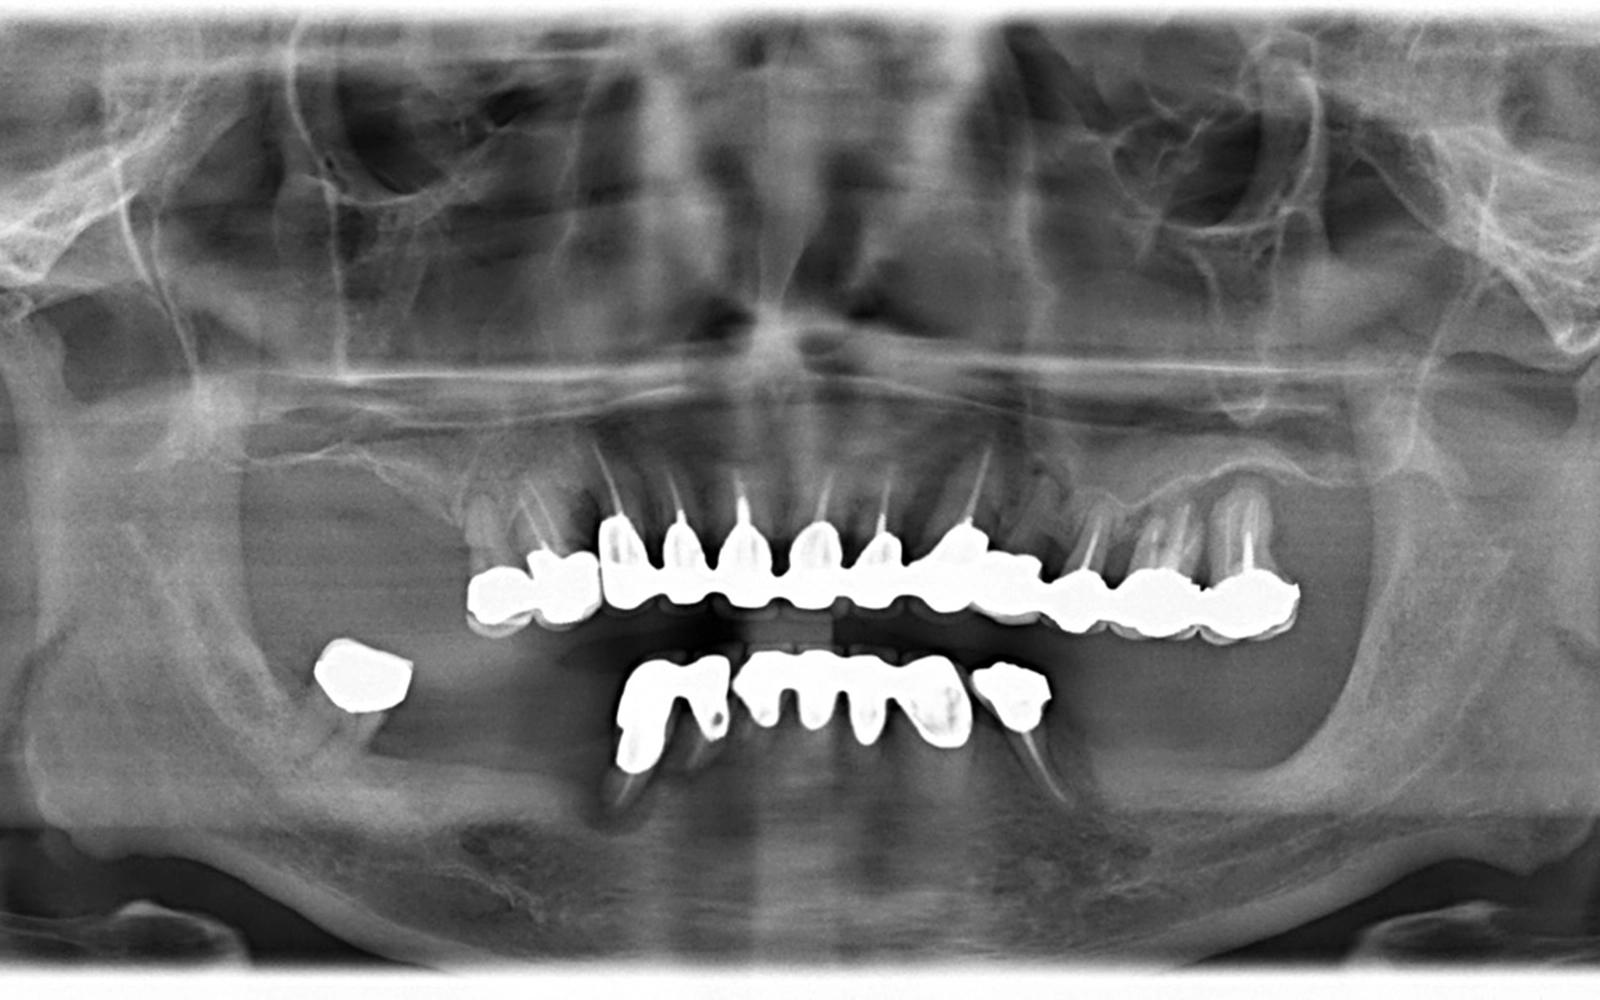

レントゲン写真では、上顎に多数の金属製の被せ物が確認できます。レントゲンでは密度の高い金属や骨は白く写り、骨が溶けて減ってしまった部分は黒く(暗く)写ります。

歯を支える骨(歯槽骨)が健康な状態では、骨が歯の根元近くまで存在しているため、根っこの部分はあまり見えません。しかし骨が溶けて減ってしまうと、その部分がレントゲン上で黒く写るようになり、歯の根っこが長く露出して見えるようになります。これが骨の吸収を確認するための見方です。

この写真では上下顎ともにその状態が見られます。特に下顎は残存している歯が少なく、骨の吸収も広い範囲に及んでいるため、残っている歯での噛み合わせの維持が難しい状態でした。

治療前後のレントゲン写真を比較すると、治療前は上下顎ともに歯を支える骨(歯槽骨)の吸収が進んでおり、歯の根元が長く露出して見える状態でした。

下顎は残存している歯が少なく、骨の減少も著しいため、そのままの状態での噛み合わせの維持が難しい状況でした。